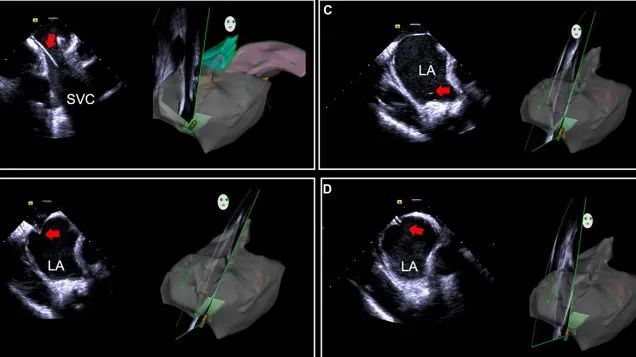

一種與心導(dǎo)管檢查相結(jié)合的超聲心動(dòng)圖診斷新興技術(shù),通過(guò)將超聲探頭置于心腔內(nèi)部,發(fā)射并接收超聲信號(hào),來(lái)精確獲取心臟解剖結(jié)構(gòu)、心臟血流動(dòng)力學(xué)等信息的實(shí)時(shí)成像。與其他影像技術(shù)相比,ICE技術(shù)具有操作簡(jiǎn)單、無(wú)輻射、安全性高、手術(shù)效率高、實(shí)用等優(yōu)勢(shì),ICE在很大程度上有望取代經(jīng)食道超聲心動(dòng)圖(TEE),成為電生理和結(jié)構(gòu)性心臟病領(lǐng)域的理想成像方式。

目前ICE技術(shù)已被應(yīng)用于左心耳封堵、房顫射頻消融、二尖瓣成形、房間隔缺損封堵等多種心臟介入手術(shù),應(yīng)用場(chǎng)景主要圍繞心臟電生理、結(jié)構(gòu)性心臟病等領(lǐng)域,目前以電生理應(yīng)用為主。數(shù)據(jù)顯示,我國(guó)結(jié)構(gòu)性心臟病介入器械市場(chǎng)規(guī)模已從2017年的4億元增長(zhǎng)至2021年的20億元,年復(fù)合增長(zhǎng)率達(dá)48.3%;預(yù)計(jì)到2025年,該市場(chǎng)規(guī)模將達(dá)到104億元,可以預(yù)見(jiàn)ICE市場(chǎng)規(guī)模也將同步高速增長(zhǎng),未來(lái)市場(chǎng)發(fā)展空間廣闊。

心腔內(nèi)超聲(ICE)技術(shù)壁壘極高,國(guó)內(nèi)主要廠商核心部件仍舊為進(jìn)口,集成了超聲和圖像處理最前端技術(shù),包括超聲探頭、線纜、軟件成像算法等,是當(dāng)前內(nèi)窺超聲方向最具挑戰(zhàn)的領(lǐng)域。ICE的應(yīng)用經(jīng)歷了2D平面成像、3D三維立體成像、以及4D的實(shí)時(shí)三維立體成像階段。